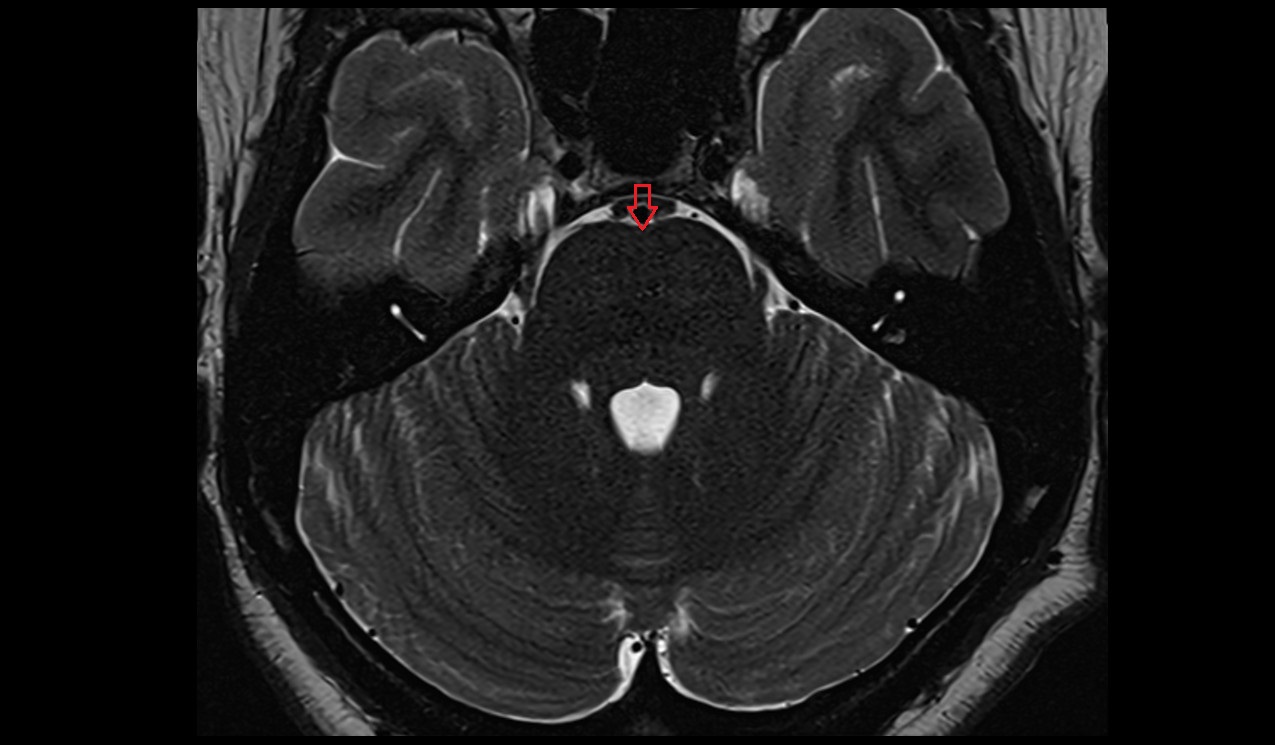

- Cerebellum

- Primary fissure

- Cisterna magna